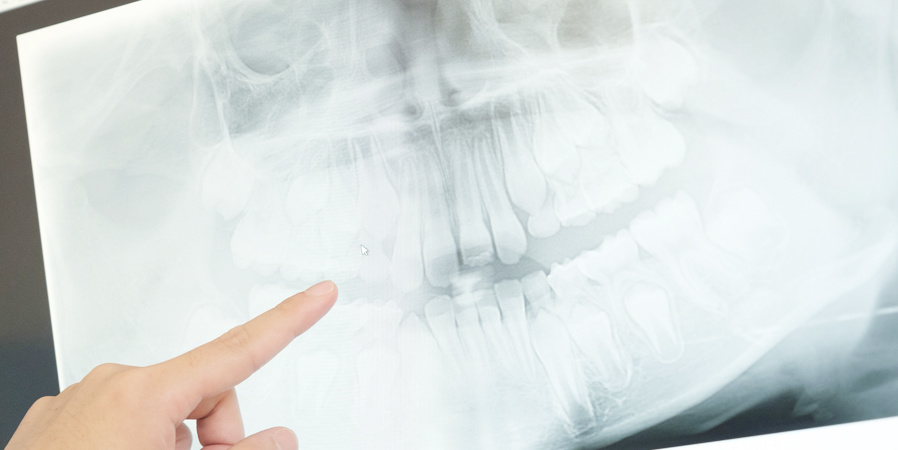

親知らずは適正な位置にまっすぐ生え、噛み合わせにも悪い影響を及ぼしていないケースでは慌てて抜歯することは必要ありません。しかし、たとえ痛みがなくても位置や向きにより、手前の歯が圧迫されて歯並びを崩してしまうこともあります。それが酷くなるととても激しい痛み・腫れが生じ、腫れがひどくなると口が開けられない、飲み込む時に痛むなど、日頃の生活に支障が出ることもあります。僅かでも気掛かりな症状があれば、悪化する前にできる限り早くご相談することをおすすめします。もし抜歯になった際にも、はこぎ歯科では歯科用CTを使用した正確な診断が可能のため、安心して治療を受けていただけます。